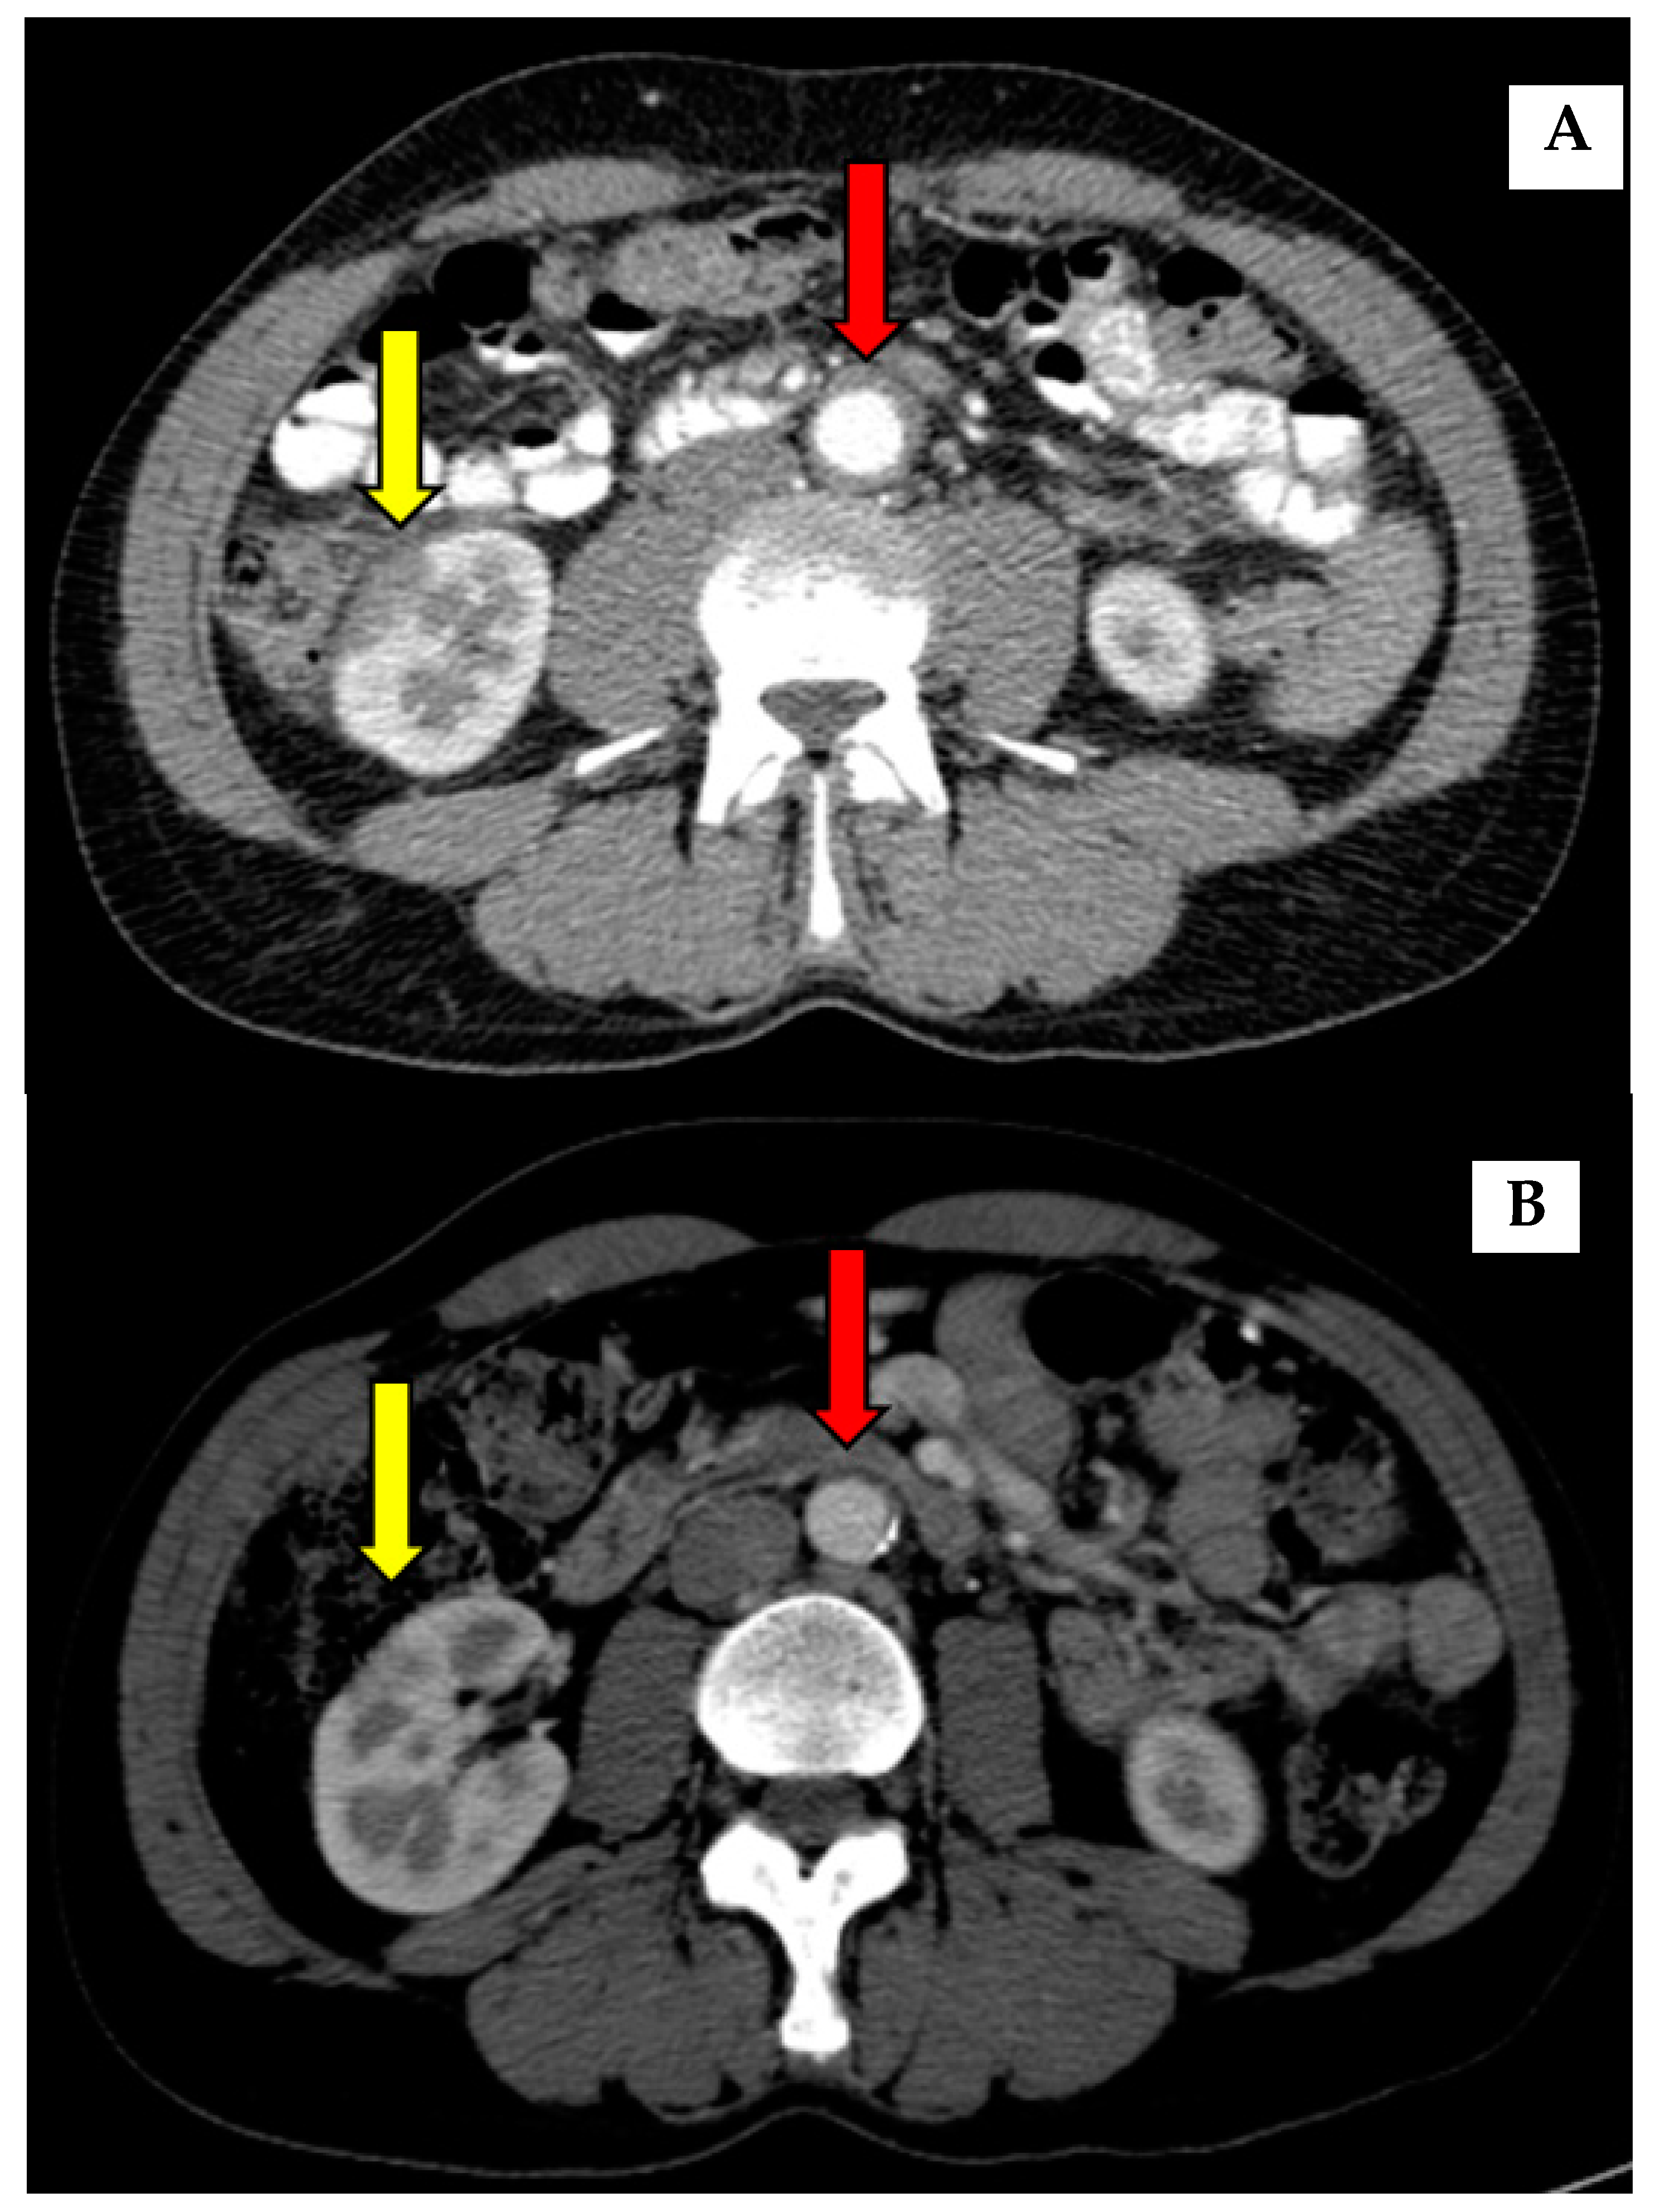

| 1 | male | 75 | Type 1 | 4 years after AIP diagnosis: asymmetric thickening of aorta wall (up till 5 mm) in infrarenal part of aorta | Rituximab and CST 10 mg | Former (30 PY) |

| 3 | male | 57 | Type 1 | At the time of AIP diagnosis: circumferential thickening of aorta wall | Rituximab | Never |

| 8 * | male | 85 | Type 1 | At the time of AIP diagnosis: imaging signs of periaortitis | Previously treated with CST, currently no treatment | Former (10 PY) |